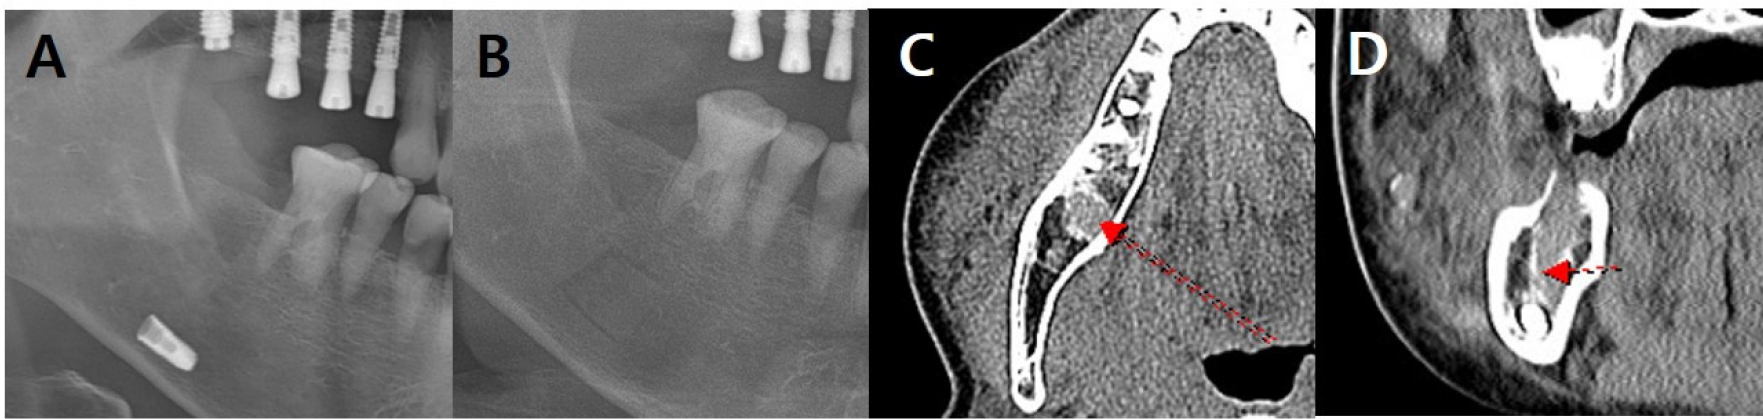

Fig. 1.

Radiographic findings in case 1 at the first visit. (A) Panoramic radiograph shows the implant in the right mandible, (B) Panoramic view after implant removal. Because the image was taken immediately after surgery, a bony window line is observed. (C, D) Coronal and axial CT images showing increased attenuation leading to the fixture. Loss of buccal cortical bone in the #47 area is observed, suggesting a post-procedural change. Diffuse swelling is observed on the buccal side of the mandible, and the mental foramen area is affected. The trajectory of the IAN is indicated by a red arrow. IAN, inferior alveolar nerve; CT, computed tomography.

A 66-year-old woman was referred from local clinic because of fixture sinking in the #47 region during implant surgery. The patient had a brain aneurysm and carotid arteriosclerosis and took an antithrombotic agent. The patient complained of swelling and pain in the right mandible. Panoramic radiography showed that the implant fixture was located in the right inferior alveolar canal (Fig. 1A). CT showed the implant fixture near the inferior margin of the mandible (Fig. 1C) and buccal cortical bone loss at the #47 site with increased attenuation leading to the fixture (Fig. 1D). In addition, diffuse swelling was observed on the buccal side of the mandible extending to the mental foramen, that confirmed right IAN damage. Although the patient had not been previously diagnosed with osteoporosis and had no history of related medications, CT showed an osteoporotic bone pattern.